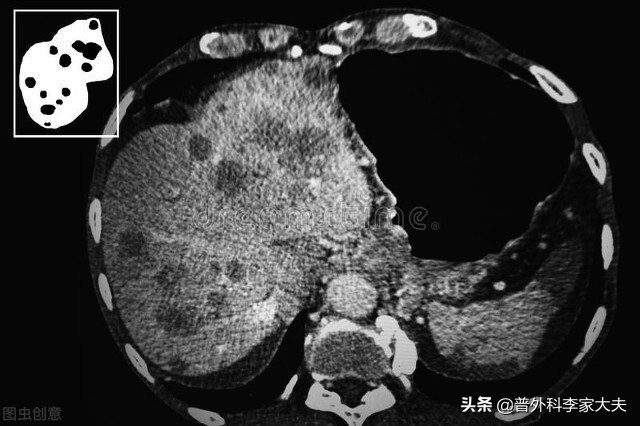

综合治疗在晚期肝癌患者中的价值:

各种肝癌的治疗方法,各有各的优势。为提高晚期肝癌患者疗效,于是上述各种治疗方法的综合应用,就成了医患共同努力的方向,为此国内外专家们进行大量临床研究,结果也不负广大晚期肝癌患者的期望。来自中山大学肿瘤防治中心2010年的大宗病例研究报道,晚期肝癌患者,采用介入化疗栓塞联合射频消融治疗的中位生存期达28个月。与大量晚期肝癌患者只有2-3个月的生存期对比,则有惊人的疗效提高。

肝癌